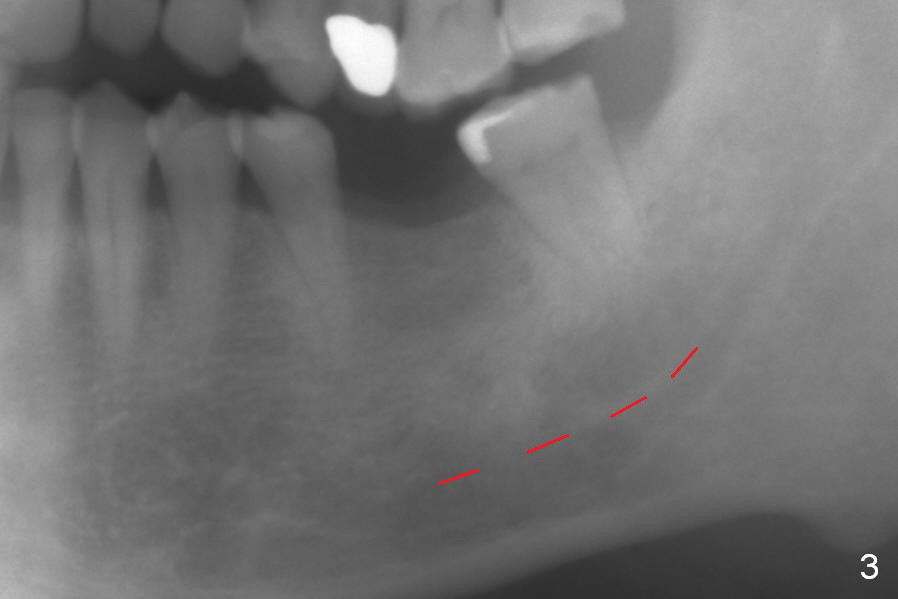

A 60-year-old man has lost the tooth #19 for approximate 20 years (Fig.1). The superior border of the Inferior Alveolar Canal is not distinct in PA. An implant that is slightly longer than the root of the neighboring tooth should be safe (Fig.2). Panoramic X-ray reveals plenty of bone height (Fig.3). Therefore, initial osteotomy depth will be 10 mm. Insert a parallel pin and take the 1st intraop PA for depth confirmation. If there is enough bone to place a 14 mm implant (Fig.4), but the crestal width is insufficient, place a 12 mm implant subcrestally to prevent thread exposure.